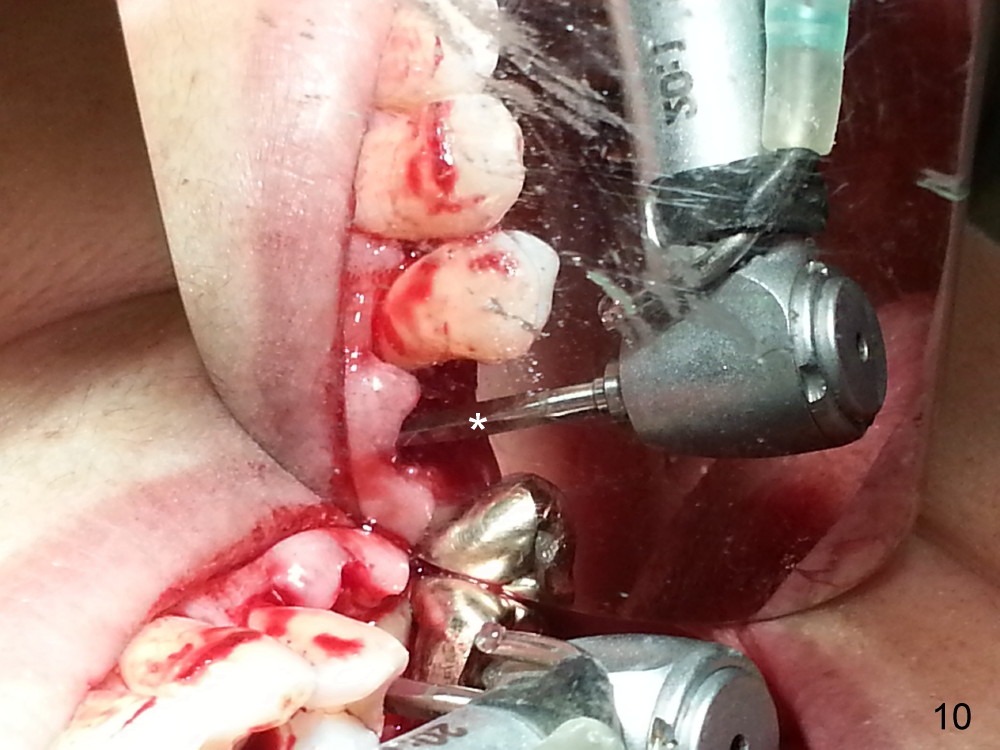

The tooth #13 appears to be affected by periodontits and occlusal trauma (Fig.1*). After using a periotome (Fig.2), the tooth is extracted (Fig.3). The buccal flap is raised (Fig.4). Gingival graft is to be harvested from the site of #15 (Fig.5). The tissue is elevated buccally (Fig.6) and separated (Fig.7). The donor site is covered by a collagen membrane (Fig.8*). A diamond bur is used to induce bleeding from the socket (Fig.9*). Osteotomy is initiated (Fig.10) and enlarged (Fig.11,12). A tapered implant is being placed (Fig.13-15) following internal sinus lift (Fig.16,17). The implant is placed subcrestally, followed by bone graft (Fig.18), soft tissue graft (Fig.19), and suturing (Fig.20 <, Fig.21).